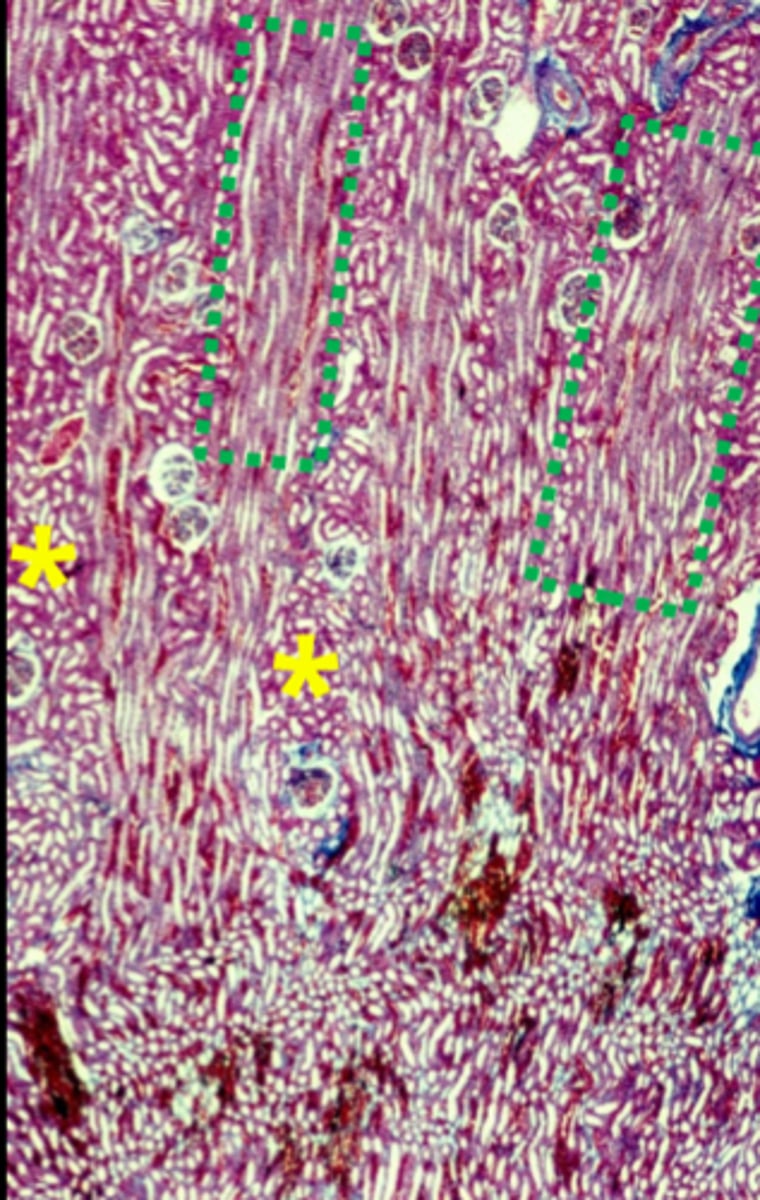

what is in the medullary rays

straight tubules and collecting ducts (green boxes)

what is in the cortical labyrinth

convoluted tubules, and glomeruli

what is in the medullary rays 2

proximal and distal straight tubules

arched collecting tubules and straight collecting tubules

the medullary rays are only in the ___________ of the kidney